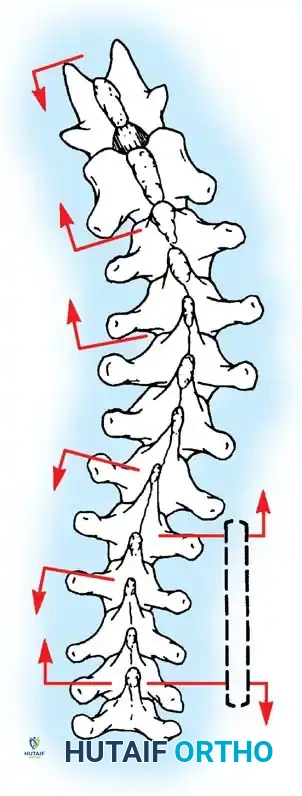

- Direction of Dissection: It is anatomically advantageous to dissect from caudad to cephalad. The short rotator muscles (multifidus and rotatores) and ligaments of the spine attach obliquely, pointing superomedially. Sweeping upward works with the grain of these fibers, allowing for a cleaner, faster subperiosteal release.

Lateral Exposure and Hemostasis

- Transverse Process Exposure: Extend the subperiosteal dissection laterally, first exposing the facet joints, and then continuing out to the tips of the transverse processes bilaterally.

- Segmental Vessels: As you dissect lateral to the facet joints, you will encounter the posterior branches of the segmental vessels. These must be meticulously identified and coagulated with bipolar or monopolar cautery to prevent insidious bleeding.